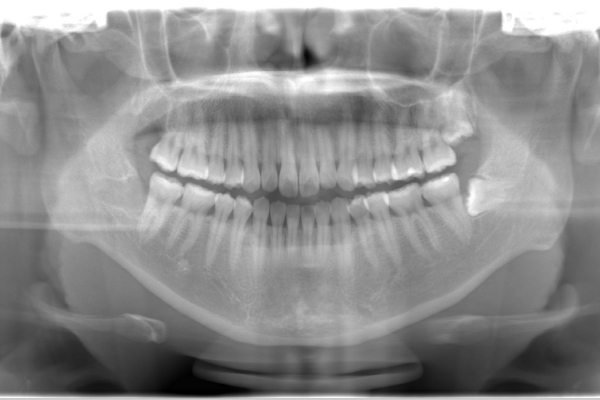

インプラントの症例 インプラントの症例

治療前〜治療後のレントゲン写真

患者様の要望奥歯にインプラント治療したい

治療期間4ヶ月

治療費用880,000円

治療内容左上奥歯に2本インプラント埋入

治療のリスクネジが緩む可能性あり